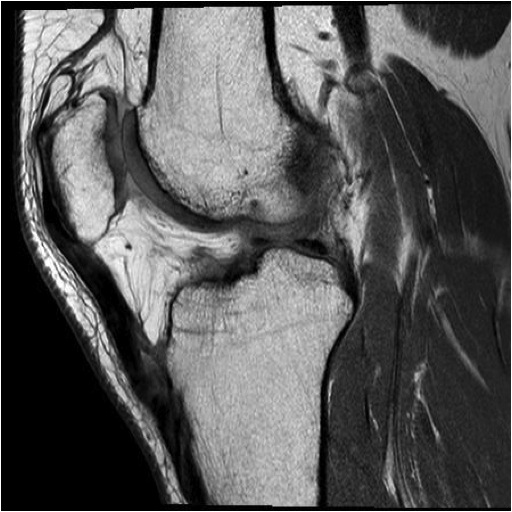

MRI

Palpable gap in tendon

Haemarthrosis